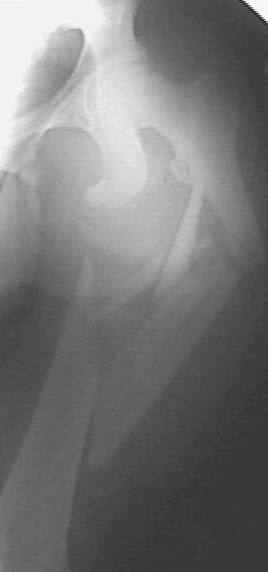

Больной 20 лет. Автодорожная авария 06.07.03.

Диагноз : оскольчатый сегментарный перелом правого бедра. Перелом лобковой кости со смещением, разрыв лобкового сращения.Планируем остеосинтез бедра пластиной. (гвоздей с блокировкой нет). Сшивание симфиза.Как поступить с переломами лобковой кости? Сергей ЗыряновНСО г. Куйбышев

Такое смещение в переднем отделе невозможно без повреждения задних отделов, а стабильность таза в основном они и обеспечивают. Что-то там неладно в области правого крестцово-подвздошного, и смещение по вертикали есть. Снимки плохого качества, трудно разглядеть, на перелом крестца похоже. Сдлать бы еще и inlet, то есть фас с направлением луча с краниальной стороны градусов 30-40 от вертикали.